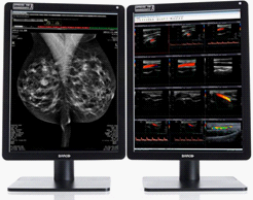

Mammograafiline diagnostika nõuab detailide võimalikult täpset taasesitamist nii ekraani eraldusvõime kui pildikvaliteedi osas. Seetõttu kasutatakse siin kahe/mitme monitoriga süsteemides 5 MP/6 MP monitore ja ühe monitoriga süsteemides 12 MP monitore. Need on varustatud uusimate ja arenenumate tehnoloogiliste lahendustega, mis kontrollivad pidevalt pildiparameetreid võimalikult suure täpsusega. Seetõttu saab neid monitore kasutada kõigi tehtud uuringute kirjeldamiseks (multimodaalsuse monitor).

Suurema pildindusvälja tõttu näeme kahe monitoriga jaamades suundumust asendada 5MP monitorid 6MP monitoridega. Ühe monitoriga (kombineeritud) jaamade jaoks on nüüd saadaval ainult 12 MP monitorid, kuna 10 MP monitoride tootmine on lõpetatud.

Pakkumine (ühe ekraaniga jaamad):

BARCO Nio Fusion 12MP MDNC-12130

- Diagonaal ja eraldusvõime: 30,9 tolli (784 mm), 12 MP (4200 x 2800), konfigureeritav järgmiselt: 2 x 5,8 MP (2 süsteemi 2100 x 2800)

- Heledus ja kontrastsus: 1200 cd/m² (600 cd/m² DICOM), 1500:1 paneel: IPS, värviline, 30-bitine (3 x 10 bitti värvi kohta)

- Riistvara kalibreerimine DICOM Part14 jaoks MediCal QAWeb tarkvaraga

- Signaaliliides: DisplayPort 1.2 x 2, USB 2.0 jaotur (tüüp A x 2, tüüp B x 2)

- Peegeldusvastase kaitsepaneeli valik

- Garantii 5 aastat, taustvalgustuse süsteemile 40 000 tundi

BARCO Coronis Uniti 12MP MDMC-12133

- Diagonaal ja eraldusvõime: 33,6 tolli (853 mm), 12 MP (4200 x 2800)

- Heledus ja kontrastsus: 2100 cd/m² (1000 cd/m² DICOM), 1200:1

- Paneel: IPS, värviline, 30-bitine (3 x 10 bitti värvi kohta)

- Riistvara kalibreerimine DICOM Part14 jaoks MediCal QAWeb tarkvaraga

- Signaaliliides: DisplayPort 1.2 x 1, USB 2.0 HUB x 3

- Peegeldusvastase kaitsepaneeli valik

- Garantii 5 aastat, taustvalgustuse süsteemile 40 000 tundi